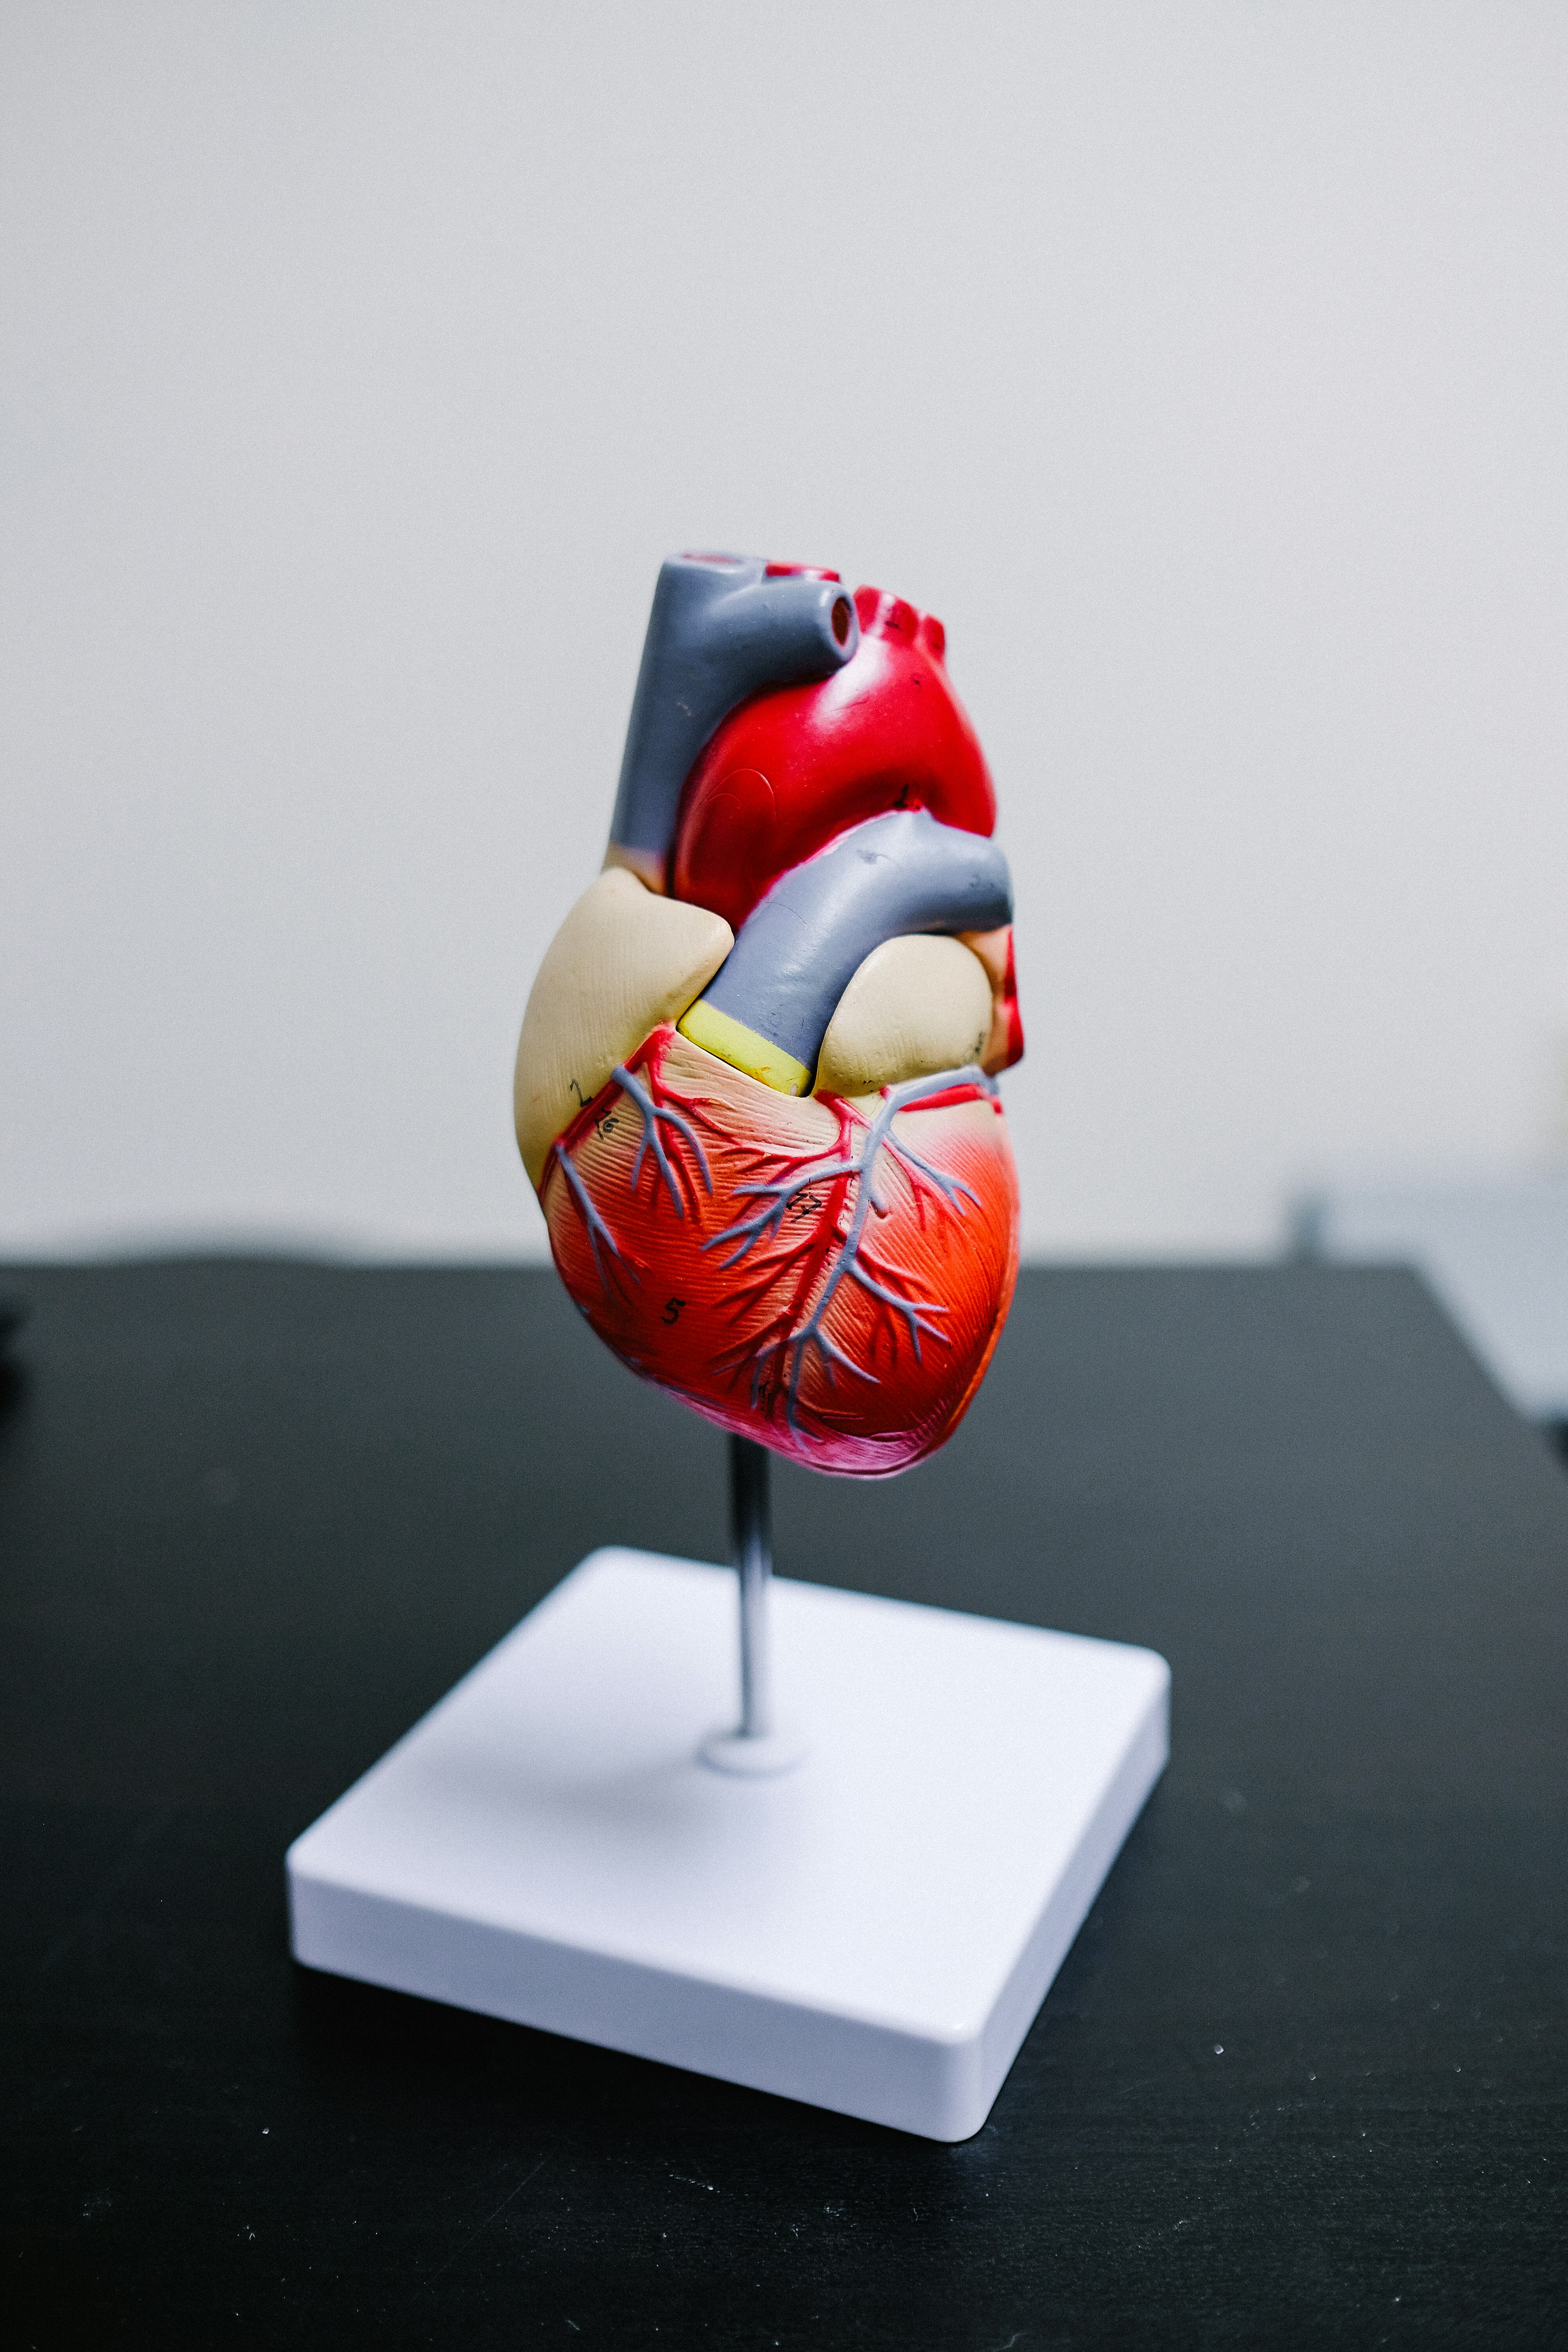

Bridging the gap between world-class medical expertise and global patients. High-precision surgery at lower costs than Western alternatives.